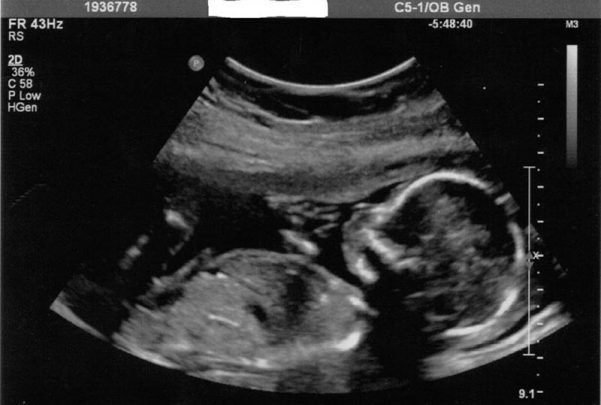

El test forma parte del servicio de cribado neonatal y permite la búsqueda de aneuploidías o anomalías cromosómicas en los bebés no natos mediante el análisis de la sangre de las futuras madres. Este estudio se desarrolla a través de un proceso no invasivo, por lo que tiene la ventaja de que permite detectar problemas genéticos en el feto sin riesgo para la gestante, ni para su hija o hijo.

El diagnóstico prenatal comienza con la realización de un cribado inicial, durante el primer trimestre del embarazo, en el que se estudia el riesgo de síndrome de Down o de síndrome de Edwards. Según su resultado, se decide si es necesario ofrecer a la gestante la opción de llevar a cabo un análisis más pormenorizado a partir de la consecución de material genético.

Esta obtención de material se puede realizar mediante procedimientos más o menos invasivos, siendo el test de aneuploidías uno de los más seguros al no requerir más que muestra de sangre de madre. Pero para que la prueba sea efectiva es necesario procesar posteriormente esa muestra mediante técnicas de bilogía molecular que son, precisamente, las que ya se pueden abordar con los medios existentes en el laboratorio de genética del Hospital Universitario Río Hortega.